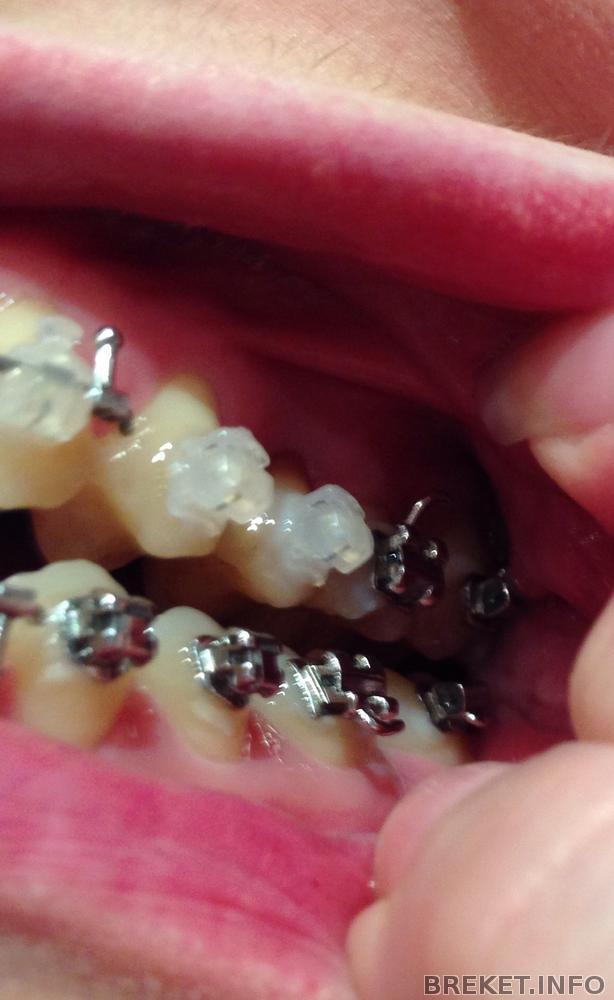

Два месяца позади, первая смена дуги.

брекеты коронки на верхние единички

Ситуация "до", спустя неделю после установки, спустя два месяца после установки (плюс смена дуги). Прикус прямой.

Первая дуга в сравнении со второй прямоугольной вела себя гораздо "скромнее". Стою в магазине и думаю, что же я хочу съесть на ужин?

Потом понимаю, что не стоит себе льстить и преувеличивать возможности. Ставим вопрос по-иному - что же я МОГУ съесть?)))) Читать далее »